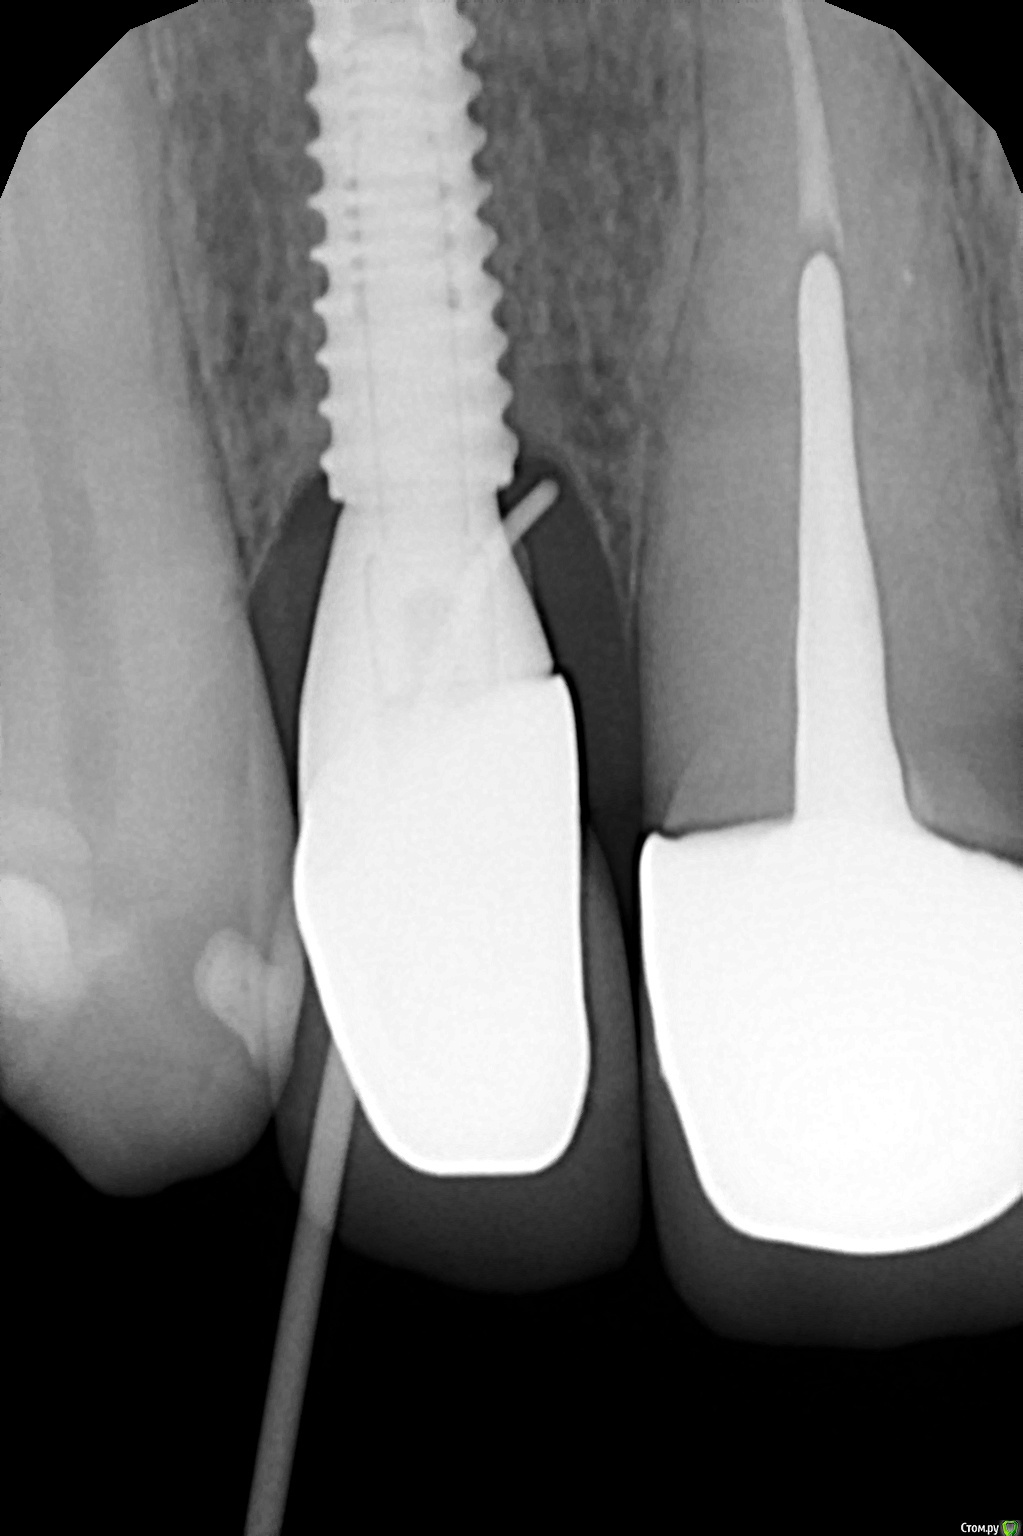

bullbull Опубликовано 18 декабря, 2018 Поделиться Опубликовано 18 декабря, 2018 Винт в позиции 11, имплантация около года назад, протезирование примерно полгода как.На контрольном осмотре выявлен свищ в проекции 2-3 витка, при зондировании витки определяются, дальше к верхушке - кость. При внутриротовом снимке гутаперча остается на уровне платформы. Жалоб абсолютно никаких.Вопросы, два извечно русских: что делать и кто виноват? Ссылка на комментарий

___49___ Опубликовано 18 декабря, 2018 Поделиться Опубликовано 18 декабря, 2018 (изменено) Винт в позиции 11, имплантация около года назад, протезирование примерно полгода как.На контрольном осмотре выявлен свищ в проекции 2-3 витка, при зондировании витки определяются, дальше к верхушке - кость. При внутриротовом снимке гутаперча остается на уровне платформы. Жалоб абсолютно никаких.Вопросы, два извечно русских: что делать и кто виноват? МГ.JPGВас это не смущает ? Изменено 18 декабря, 2018 пользователем ___49___ 6 Ссылка на комментарий

bullbull Опубликовано 18 декабря, 2018 Автор Поделиться Опубликовано 18 декабря, 2018 Спасибо. Я думал цемент более контрастный. Зазор мог стать причиной?Задам пару вопросов своим ортопедам.Делать кюретаж с откидыванием? Косточку стоит сыпать? Ссылка на комментарий

bullbull Опубликовано 18 декабря, 2018 Автор Поделиться Опубликовано 18 декабря, 2018 Выделения незначительные. Жидкие, гнойного характера. Боли нет. Внешне никаких изменений, кроме свища. 1мм в диаметре, а то и меньше. Ссылка на комментарий

bullbull Опубликовано 20 декабря, 2018 Автор Поделиться Опубликовано 20 декабря, 2018 При зондировании определяются 2-3 витка, гнойное отделяемое. Соответственно, контакт гноя с винтом есть.Какой доступ лучше: внутрибороздковый с разрушением сосочков или горизонтальный с иссечением свища? Ссылка на комментарий